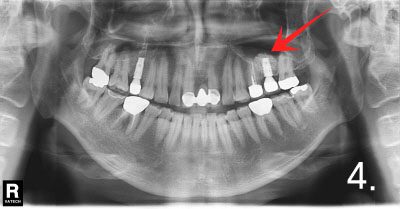

Before the surgery. There is not enough bone at back site to place implants

Implant placement and sinus bone graft were performed simultaneously on right side. Only sinus bone graft was performed on left side due to the lack of the residual bone to place implant simultaneously

Implant placement was performed a few months after sinus bone graft

All implant crowns were fabricated and delivered. All teeth functions were restored.